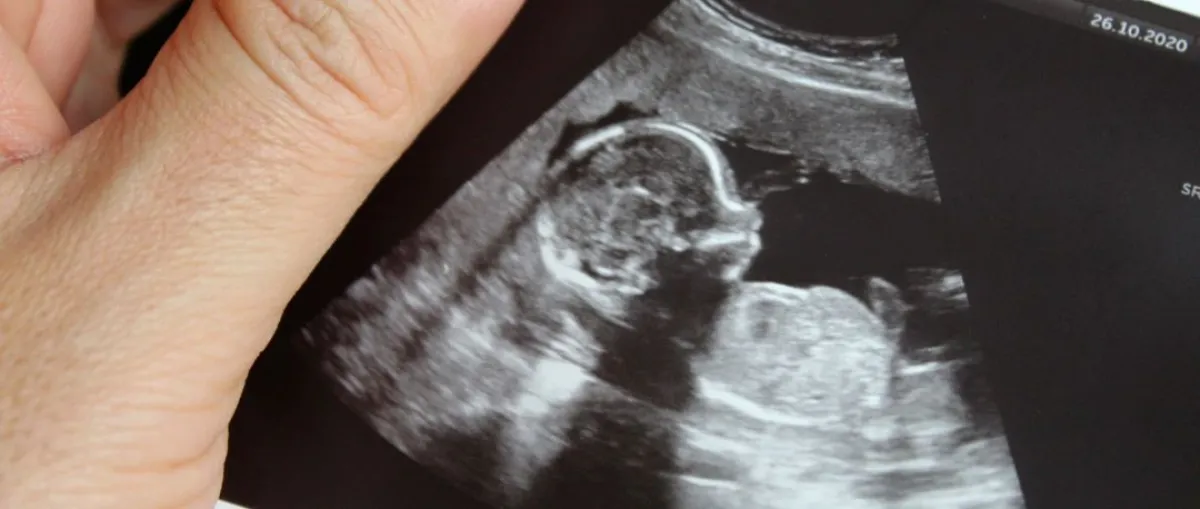

ظل الاعتقاد السائد وعلى مدى سنوات طويلة أن الجنين في مرحلة الحمل لا يفعل شيئاً سوى أن يستمد الهواء والغذاء من الأم عن طريق المشيمة، حتى ظهرت في السنوات الأخيرة دراسات تؤكد أن الإنسان يعيش حياة أخرى في رحم أمه، وعليه فيجب حساب عمر الطفل منذ أن يحدث الحمل، وليس من يوم الولادة؛ وذلك لأهمية تلك الأشهر التسعة وما يحدث بها من تغيرات وما يمر بها الجنين من تجارب، وقد التقت «سيدتي وطفلك»، في حديث خاص بها؛ الدكتورة رؤى الطاهر، استشارية طب النساء والولادة، حيث أشارت إلى مفاجآت لا تعرفينها عن حياة جنينك في رحمك خلال مرحلة الحمل كالآتي.